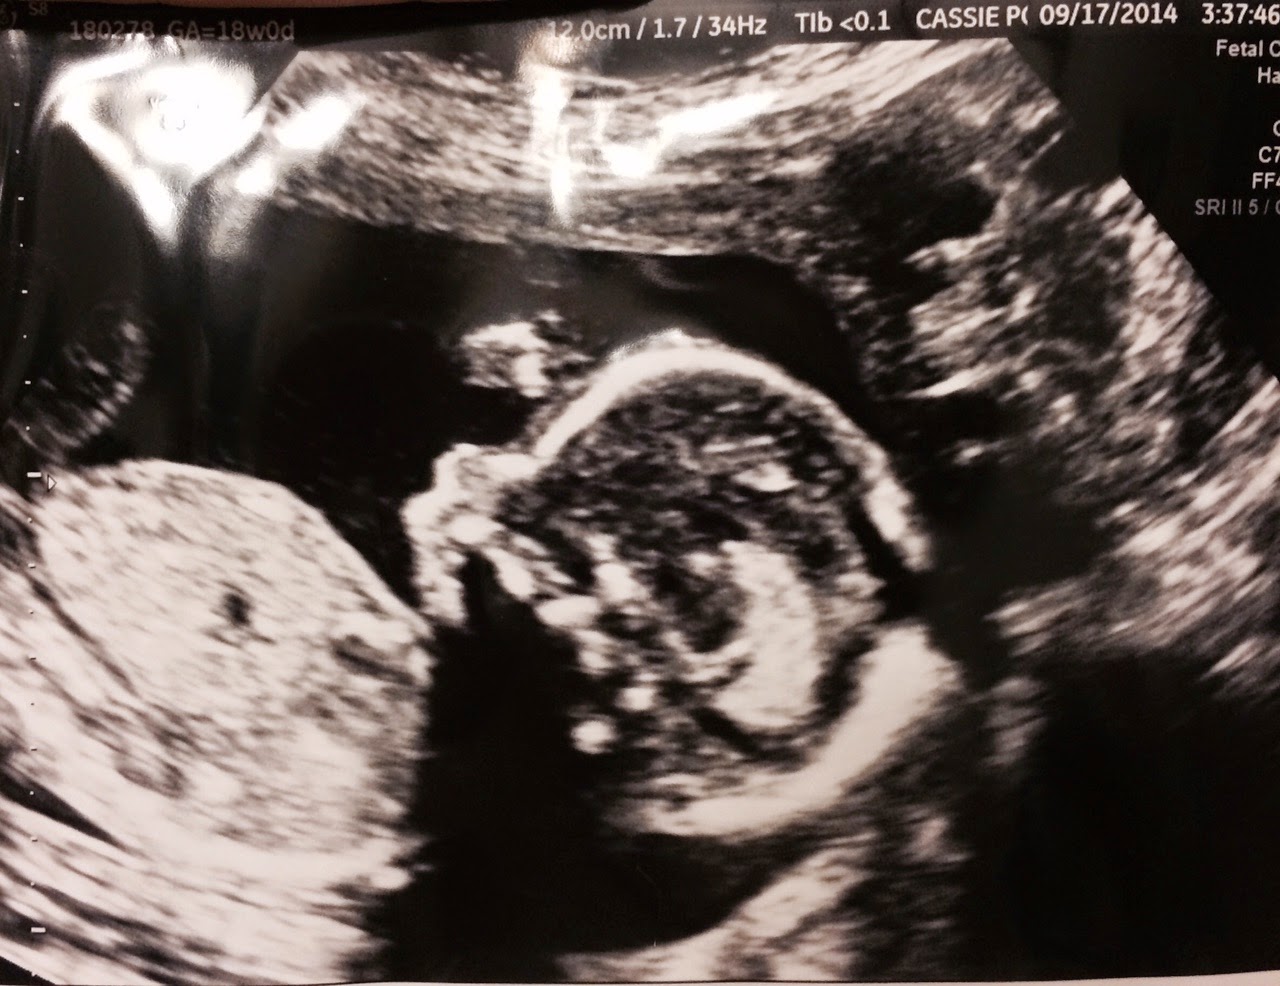

Here are a few of the ultrasounds we've had and you can really see how much he's growing. They are all profile pictures.

This was 18 weeks